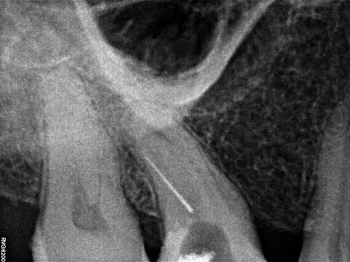

Лечение зубов под микроскопом;

Перелечивание и спасение зуба с воспалением на верхушке корня;

Прохождение корневых каналов со сложной анатомией, извлечение сломанных инструментов;